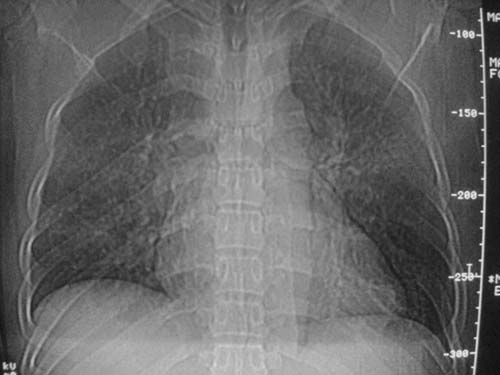

外伤病人,年龄忘了,中年人右侧肋骨骨折了,

这是刚住院拍的片子。